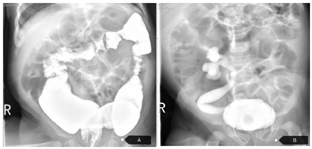

膀胱造影示:膀胱-右侧输尿管返流。心脏彩超:动脉导管未闭、动脉水平双向分流,肺动脉增宽,左心增大,三尖瓣少量分流,肺动脉高压。钡剂灌肠:先天性巨结肠可能。脑干诱发电位:双侧各波潜伏期正常,波间期正常,V波反应阈增高(左耳45dBnHL,右耳55dBnHL)。血常规示:白细胞29.18×109/L),中性粒细胞百分比81.70%,淋巴细胞百分比12.70%,血红蛋白91.00 g/L,红细胞压积28.30%,血小板591×109/L,网织红细胞百分比4.45%,网织红细胞绝对值146.80×109/L,CRP 40.98 mg/L。降钙素原3.92~4.48 ng/ml。尿常规示:白细胞45.个/ul 8-106.6个/ul,白细胞8.24个/HP-19.19个/HP,余大致正常。胸腹联合立位片示:1.腹部肠气增多伴部分肠管轻度扩张,请结合临床,2.心肺未见明显异常(图2)。免疫球蛋白G 16.1 g/L,免疫球蛋白A 0.683 g/L,余正常。血生化、脑脊液常规、脑脊液培养、头颅CT及MRI、凝血功能,甲状腺功能、血培养正常。